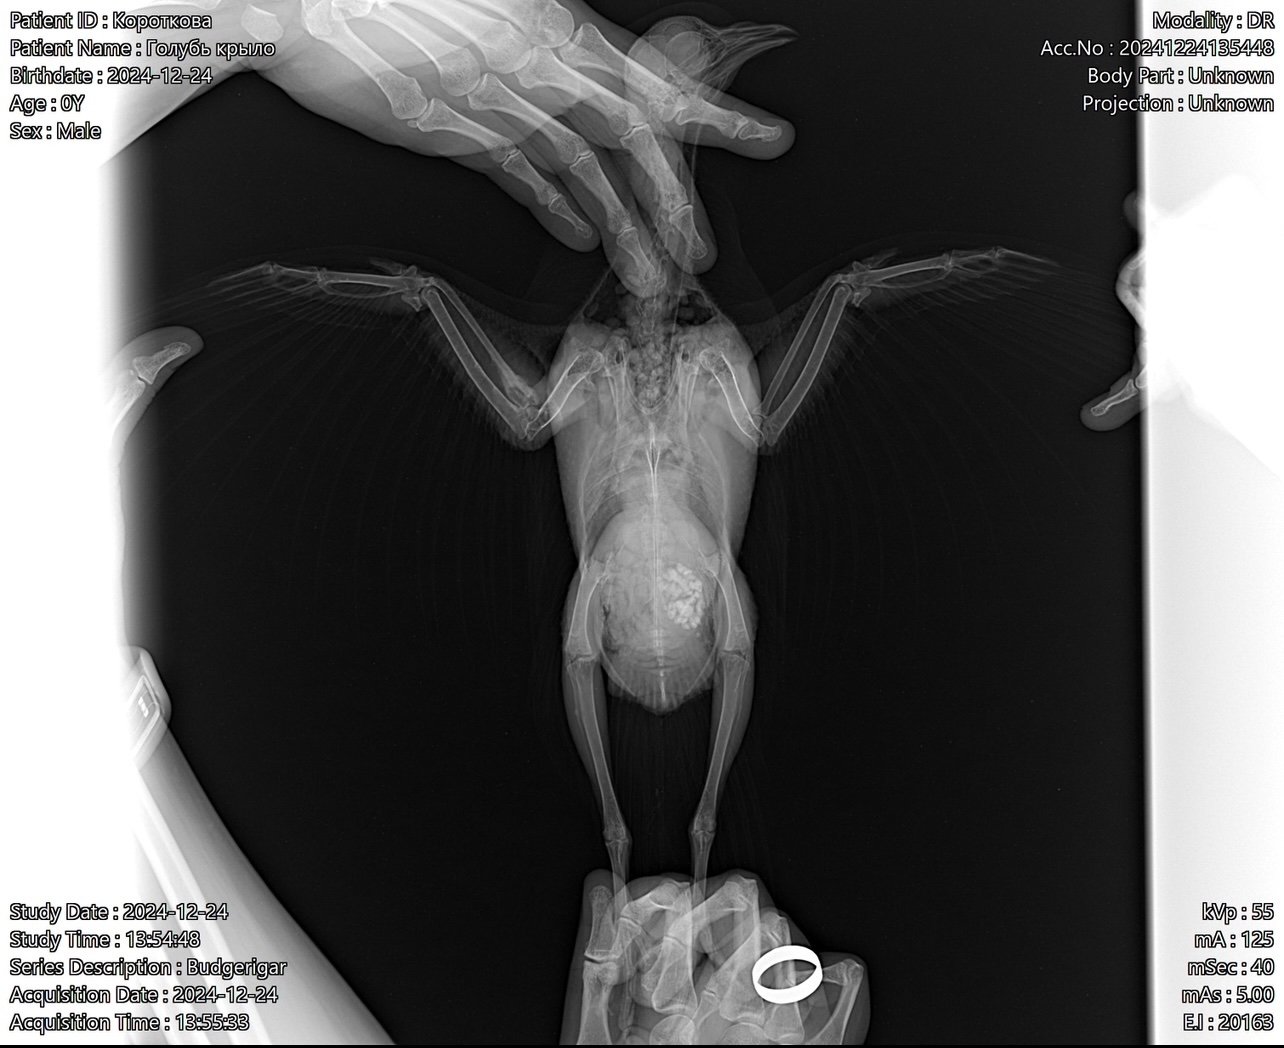

Татьяна Ладутько Опубликовано 4 января, 2025 #8 Опубликовано 4 января, 2025 @ekatereina здравствуйте. Антибиотики у вас назначены прям по самой верхней границы, даже чуть выше. Если брать вес 300гр. Ципролет - суточная 14мг выходит, а по верхней 12мг; Сумамед 25мг суточная, а по верхней 24мг, это если взять 80мг/кг@маленький принц посмотрите, пожалуйста, может немного снизить? @Ильяна в смысле "всё было хорошо"? У птицы пневмония и остеомиелит в луч.кости. Антибиотики назначены к месту. И прикрытие сильное. @Физкульт-привет! Странный вы, зачем экспериментируете на птицах с питанием, до вас это уже сделали врачи и учёные, поэтому есть составленные рационы питания, зависящие от конкретного периода жизни птицы и ее потребностей. А белок - один из самых важных составляющих питания.

Zosia Опубликовано 5 января, 2025 #18 Опубликовано 5 января, 2025 все, кроме ацинетобактер- мимо идет. Часть вообще из пробиотика (какой даете, кстати). Ципрофлоксацин- имеет очень большую "вилку" доз, от 5 до 20 мг/кг каждые 12 часов. Но указаны гриббы +++, так что нистатин вам обязателен, 60 000 ед на 100 гр веса в сутки,весь курс а\б плюс 4-6 дней. По рентгену. Остеомиелит под вопросом, хотя есть зона абсцесса Броди на лучевой кости. Птиц полетит, если все срастется. Так же- описание гнилостного запаха из глюва, что может говорить о трихомонозе. Так что плюсом- метронидазол в дозе 5 мг на 100 гр веса в сутки, не менее 12 дней. 1

ekatereina Опубликовано 5 января, 2025 Автор #21 Опубликовано 5 января, 2025 2 часа назад, ната1805 сказал: не считала дозировки на антибиотики-но бросилось в глаза витамин в12 в дозе 0, 3 мл-перебор.... суммамед пересчитала-вам назначено 25 мг в день-максимально допустимая-у меня с такой дозы-а я раз такую дозу давала-стал какать на 17 день лечение желтым-пришлось бросить... у вас еще и флук тяжелый-не забывайте-и ципрофлоксацин-прям дай бог сил вашему голубю это перенести... я не придираюсь-корм у вас какой то....так не должно быть-у вас почти одна красная чечевица.... так не кормят Это просыпанные зернышки, в миске у него перловка и зеленая гречка в основном. Но он ест мало. 9 часов назад, Zosia сказал: все, кроме ацинетобактер- мимо идет. Часть вообще из пробиотика (какой даете, кстати). Ципрофлоксацин- имеет очень большую "вилку" доз, от 5 до 20 мг/кг каждые 12 часов. Но указаны гриббы +++, так что нистатин вам обязателен, 60 000 ед на 100 гр веса в сутки,весь курс а\б плюс 4-6 дней. По рентгену. Остеомиелит под вопросом, хотя есть зона абсцесса Броди на лучевой кости. Птиц полетит, если все срастется. Так же- описание гнилостного запаха из глюва, что может говорить о трихомонозе. Так что плюсом- метронидазол в дозе 5 мг на 100 гр веса в сутки, не менее 12 дней. Спасибо! не поняла про мимо. Пробиотик никакой не даем, даже не подумала, что нужно. Какой лучше? Нистатин добавим, хорошо. Метронидазол добавлять прямо сейчас? К двум антибиотикам? Уточняю, потому что голубь мало ест с начала терапии, не станет ли ему еще хуже 1

Татьяна Ладутько Опубликовано 6 января, 2025 #22 Опубликовано 6 января, 2025 3 часа назад, Ильяна сказал: не понятна обоснованность всех этих препаратов. Сумамед от респираторки, выявлен микоплазмоз; Ципрофлоксацин от остеомиелита или абсцесса Броди; Дифлюкан- противогрибковое; Гептрал- гепатопротектор; Мелоксикам от боли. Зося ничего и не отменила, а ещё добавила метронидазол и нистатин. @ната1805 дозировки на а.б. идут даже немного выше верхней, я уже считала выше. ! И ещё раз предлагаю их снизить, т.к. курс длительный. @ekatereina если птичка плохо кушает - её обязательно нужно докармливать. У вас тяжёлое лечение, не дай бог птице похудеть! 2